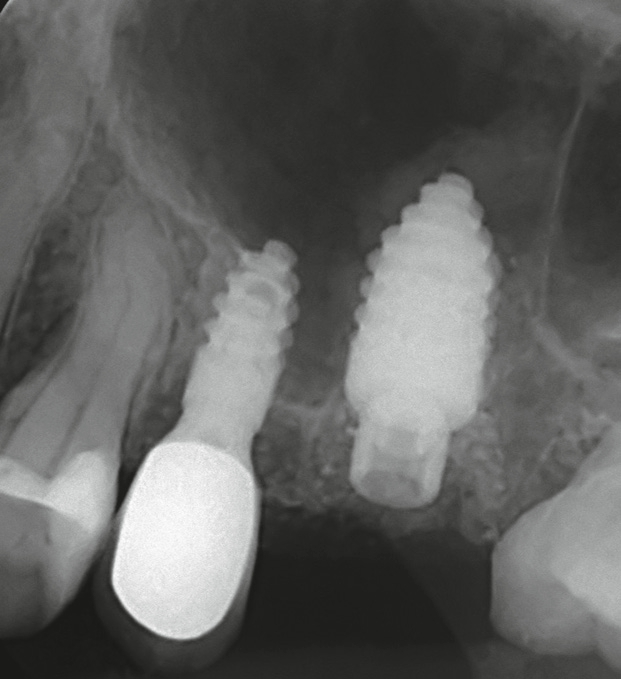

Nachdem der Behandler sämtliche Füllungs-, Wurzelfüllmaterialien sowie Zementreste von seiner Assistenz entfernen ließ, wurden die Zahnfragmente im Luftstrom der Multifunktionsspritze getrocknet und in den Champions Smart Grinder gegeben (Abb. 4). Nach wenigen Sekunden später war der Zahn zerkleinert. Es folgte eine 10-minütige Entkeimung und eine 3-minütige Neutralisation und das Augmentat war einsatzbereit. Es ließ sich sehr gut adaptieren, da es am Spatel leicht anhaftete. Autologer Dentingraft induziert nun Knochenwachstum (Abb. 5).

Glücklich verließ ich den Behandlungsstuhl, wohlwissend, welche Behandlung konventioneller Implantation mit externem Sinuslift und Einheilzeiten von bis zu einem Jahr mir erspart geblieben war. Seither bin ich begeisterter Anwender des Champions Smart Grinders. Die Abbildung 6 zeigt die Situation nach 12 Wochen.